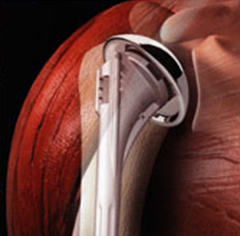

Eine Schulter-Endoprothese, auch Schulterprothese genannt, ist dem natürlichen menschlichen Schultergelenk nachempfunden. Es kann sowohl der Oberarmkopf als auch die Schulterpfanne ersetzt werden – oder beides.

Die Wahl des Implantats hängt von der Funktion der Muskulatur ab, die das Schultergelenk umgibt. Denn diese Muskeln, die sogenannte Rotatorenmanschette, führen und stabilisieren das Schultergelenk. Ist die Gelenkfläche durch Arthrose oder einen Mehrfragmentbruch zerstört, die Rotatorenmanschette jedoch intakt, brauchen wir nur die Oberfläche des Oberarmkopfes zu ersetzen. In speziellen Fällen ist die Überkleidung der Gelenkfläche der Schultergelenkspfanne (Glenoid) mit Polyethylen erforderlich.

Nach Implantation eines künstlichen Gelenkes

Nach Implantation einer Schultergelenksprothese